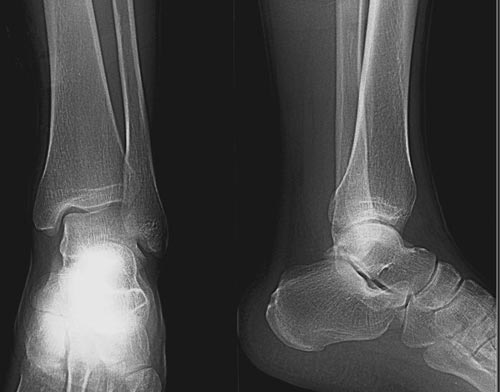

x线检查月前片示双踝关节骨质未见明显异常。一月后肿胀大部消失,疼痛稍有好转,摄片示两侧骨下段条带状高密度影,边界尚清。ct扫描示两侧胫骨下段骨皮质增厚不明显,髓腔内密度显示磨玻璃样增高,髓腔显示狭窄。

双胫骨下段近骨端处可见对称性增生硬化,骨小梁增粗但纹理尚清晰,未见明显骨质破坏,临近关节及关节囊未见明显异常。

双侧胫骨远端松质骨内见不规则密度增高影,且均以内侧为主,内侧骨皮质边缘欠清晰.临床提示月前稍运动后踝关节肿大。我考虑双侧胫骨低毒感染。

x线检查一个月前示双踝关节骨质未见异常。一个月后肿胀大部消失,疼痛稍有好转,摄片示两侧胫骨下段横行条状高密度影,边界较清。ct扫描示:两侧胫骨下段未见骨皮质增厚,两胫骨下段近骨端处可见骨小梁增粗但纹理尚清晰,未见明显骨质破坏,邻近关节及关节囊未见明显异常,软组织内未见异常.综上所诉考虑1.低毒感染所致,2.假性痛风

x线片表现为双侧胫骨下端粗条状磨玻璃样增高密度影,并可见骨皮质稍不连续。ct表现为双侧胫骨下端髓腔内磨玻璃样增高密度影,未见明显骨皮质不连续(可能与扫描体位有关)。

本例应该考虑为双侧胫骨下端应力性骨折。